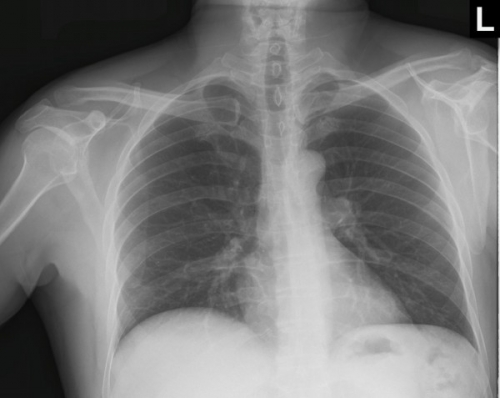

Tool to train medical student's eyes as to what a normal chest x-ray looks like, with over 500 consecutive normal images.